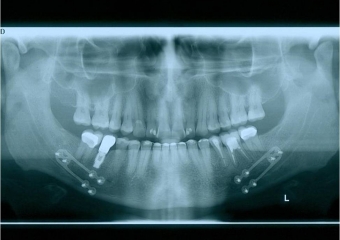

Raio x inicial